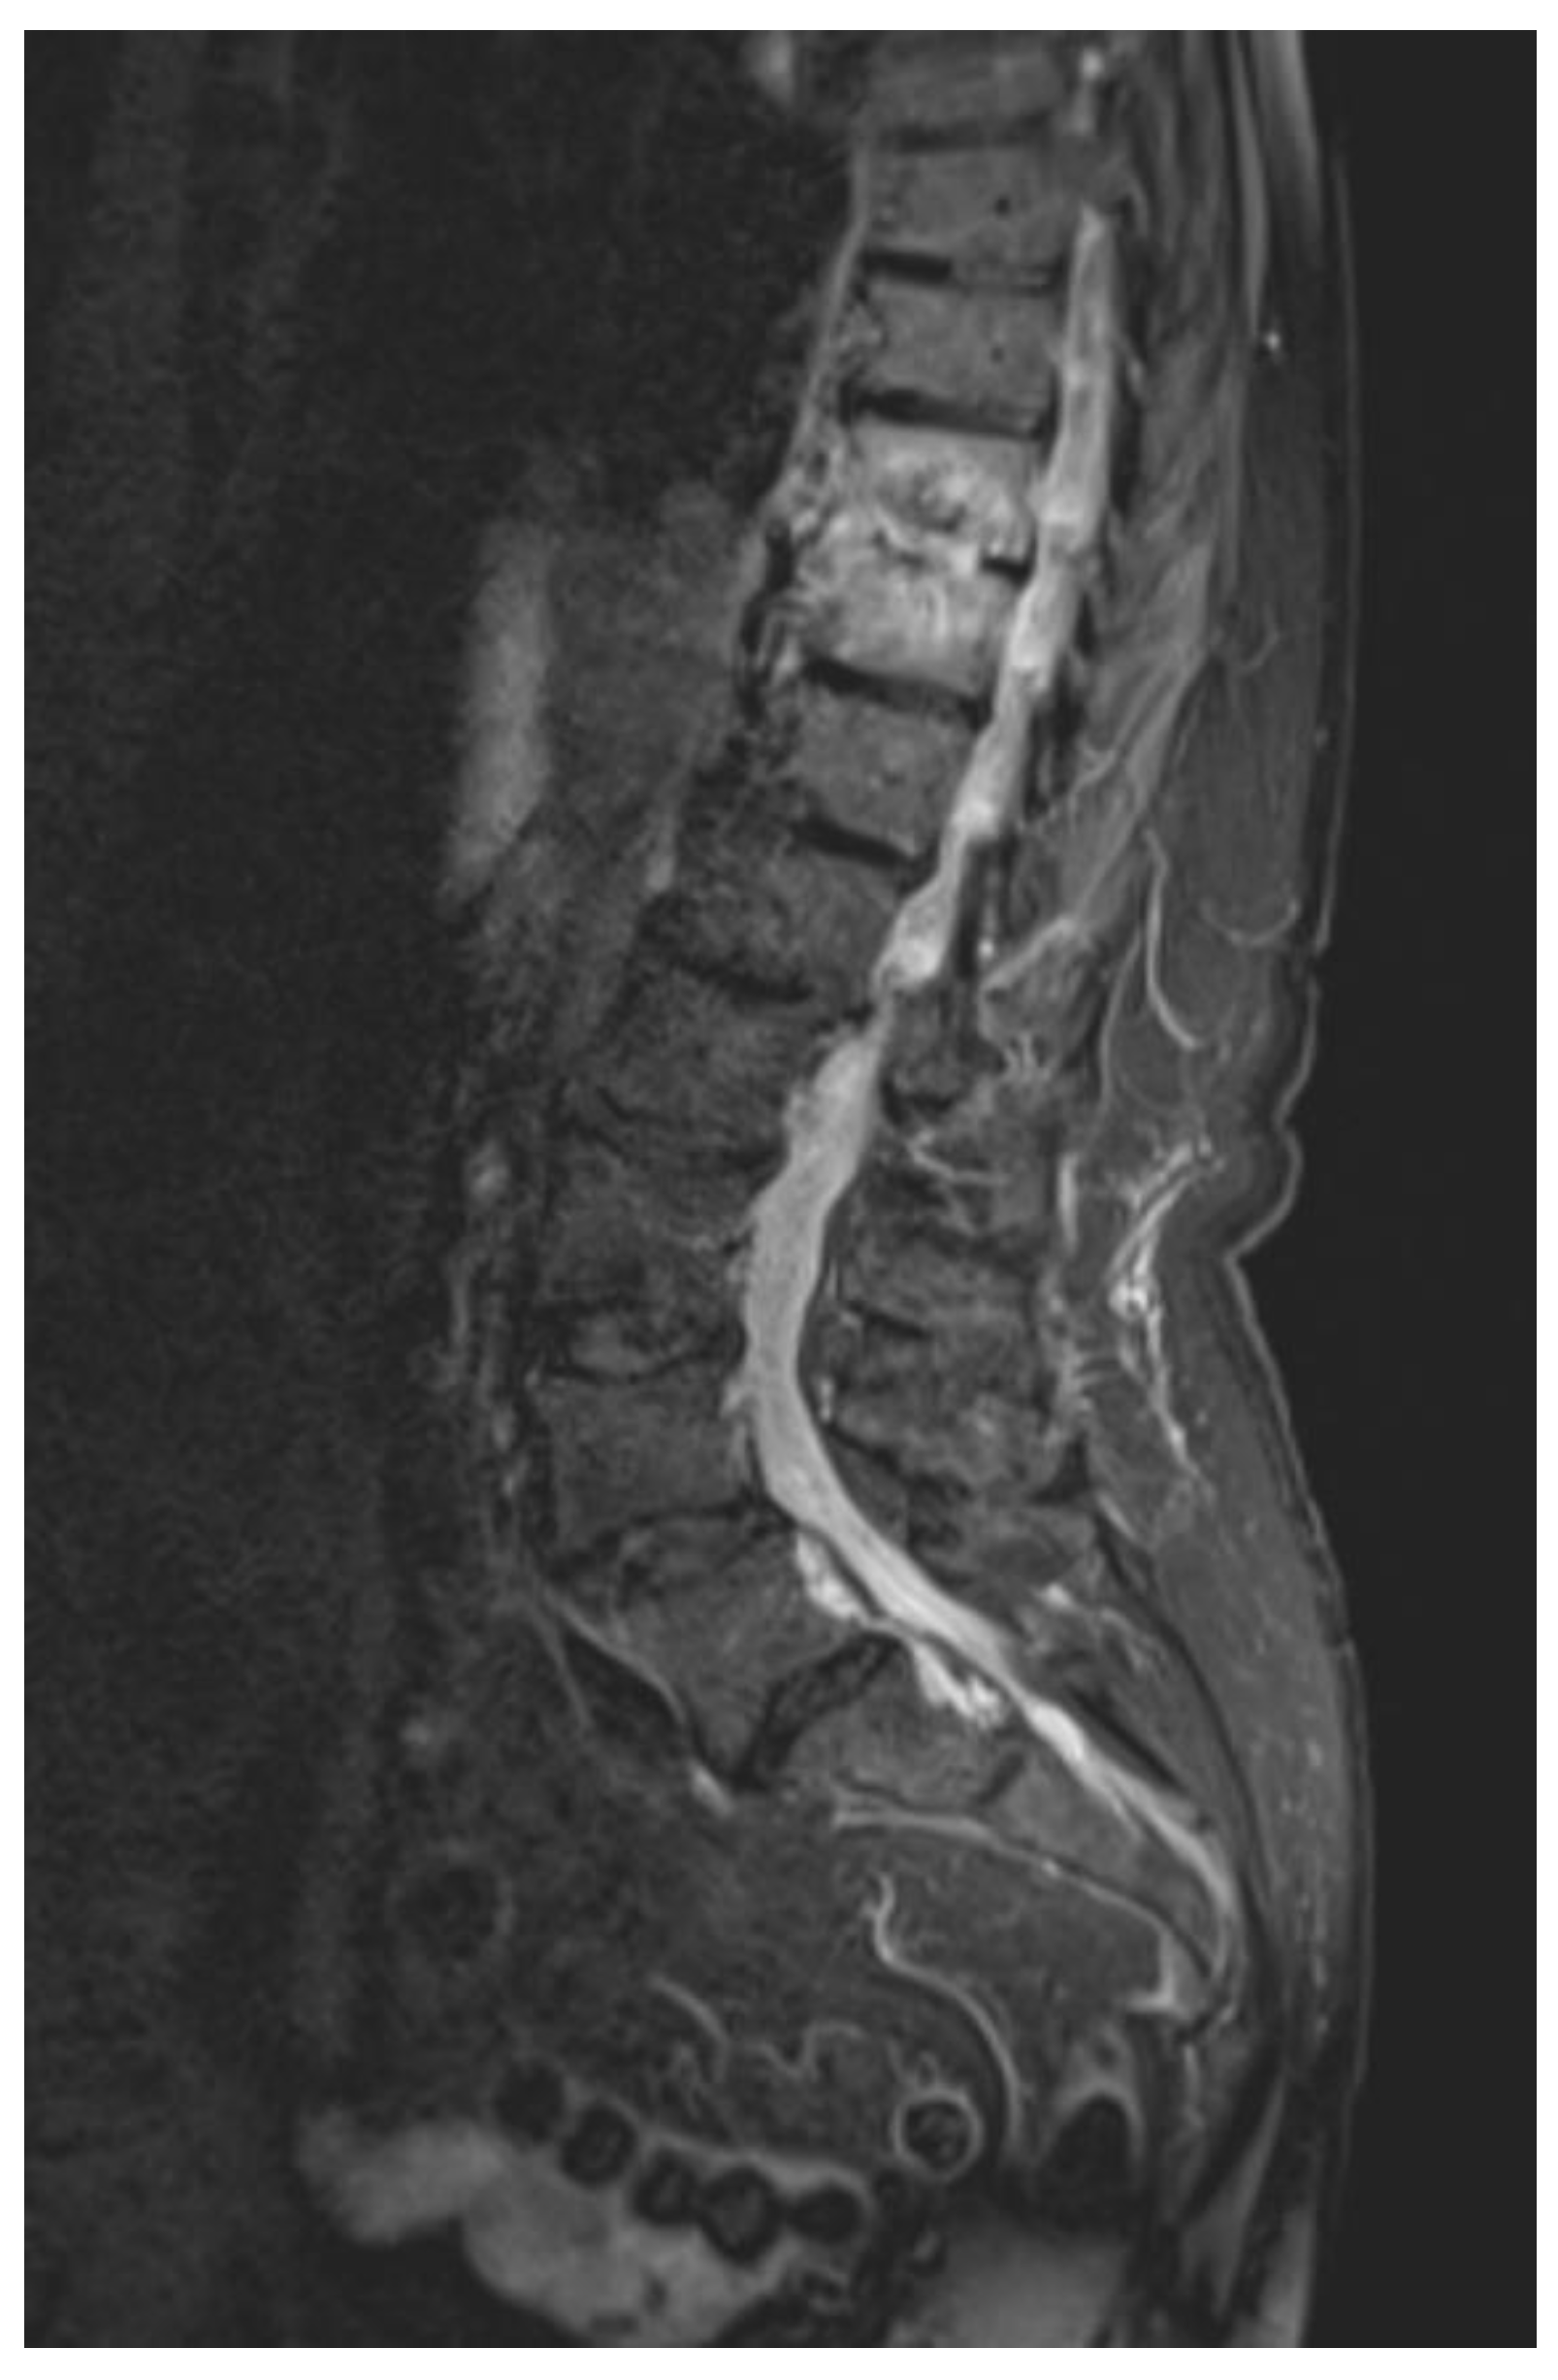

2. Case History